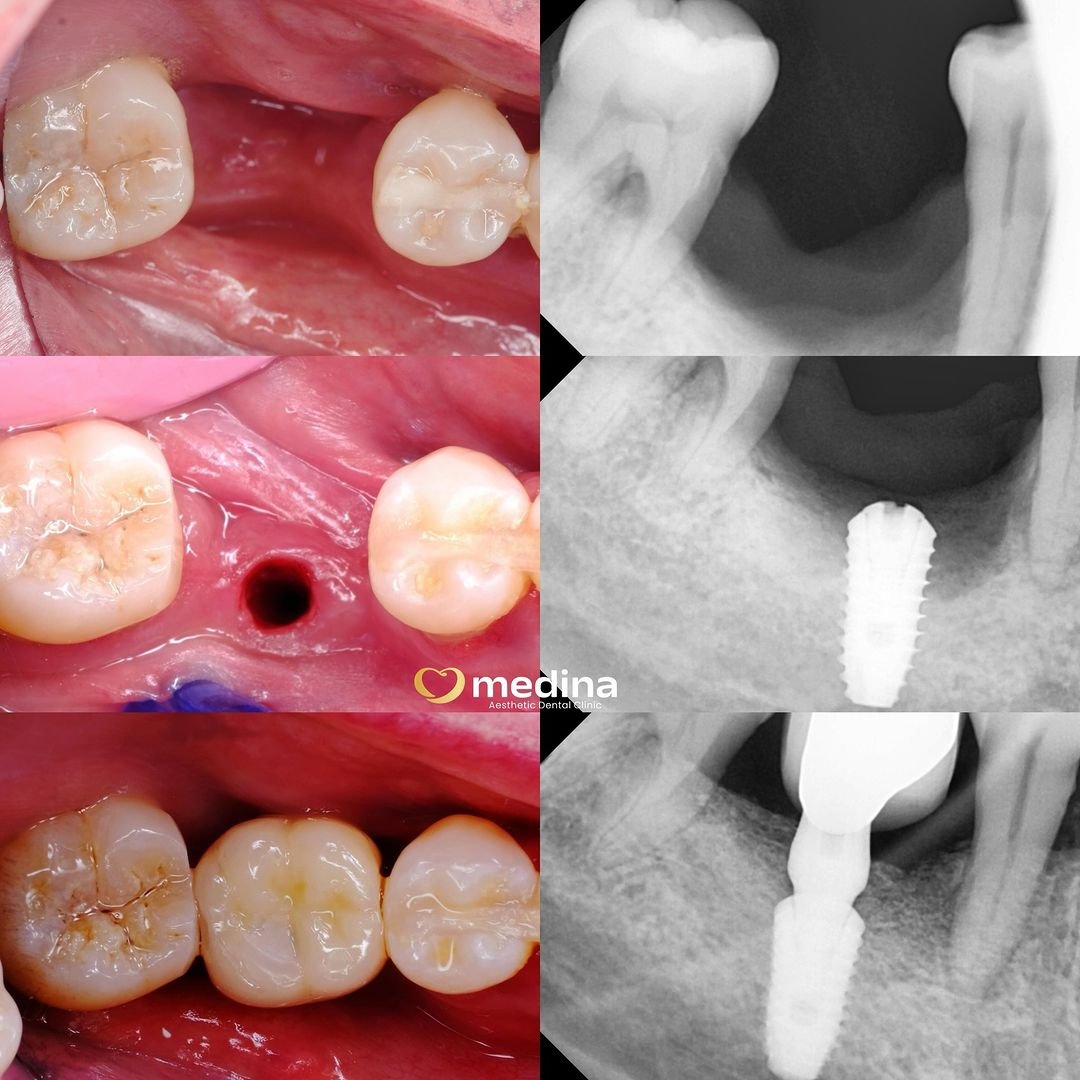

Implant adalah pemasangan gigi palsu menggunakan sekrup titanium (teknologi terbaik saat ini) didukung dengan alat rontgen/CBCT.